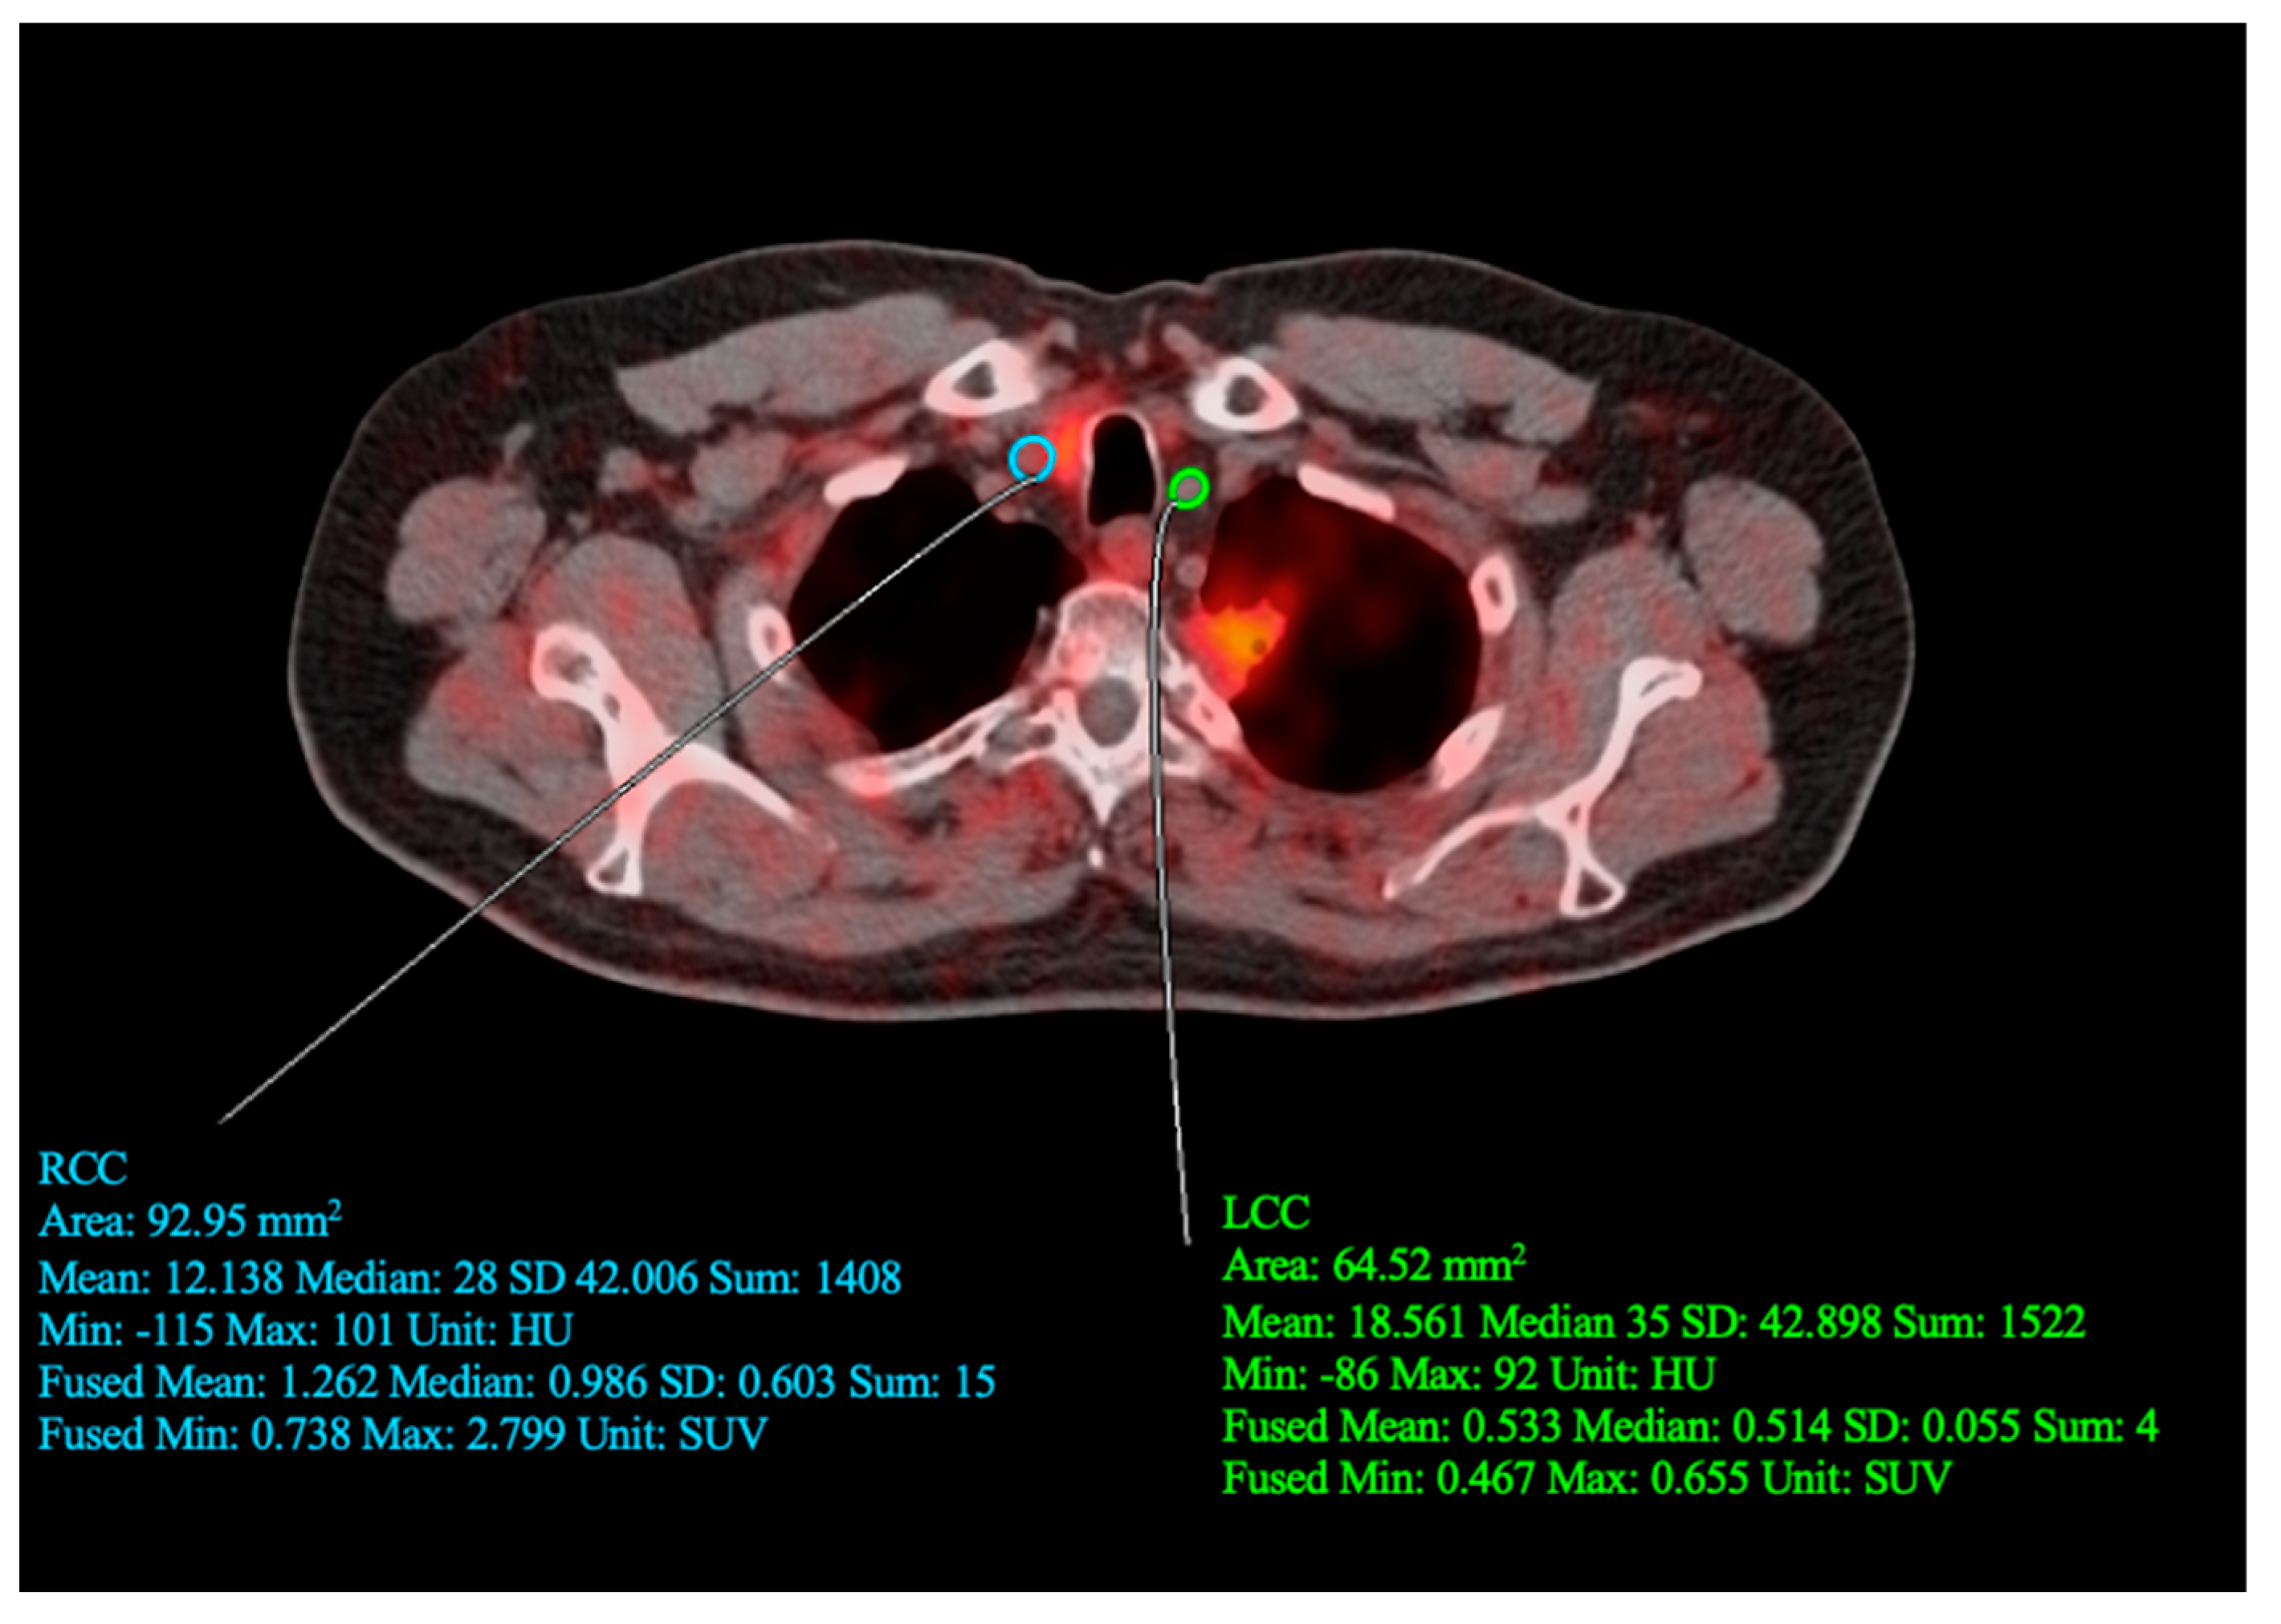

2. Case Report